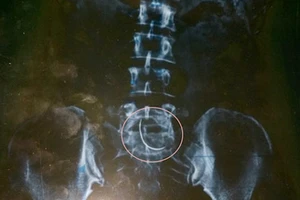

Cảnh cáo bác sĩ để kim trong bụng bệnh nhân chín năm